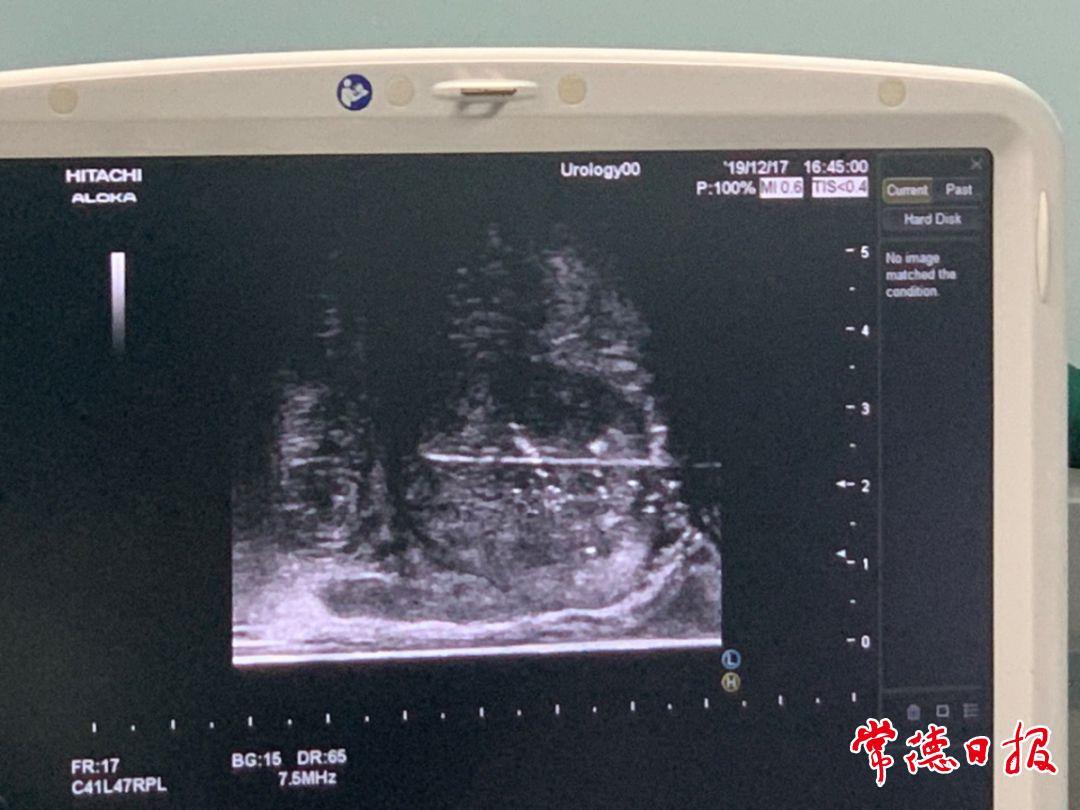

以往确诊前列腺癌多采用经直肠前列腺穿刺活检术,但这种方式需要洗肠,存在损伤直肠、出血和感染的风险。考虑到伍大爷年事已高,医院泌尿外科团队在超声科紧密配合下,为他在局部麻醉下实施了“直肠彩超引导下经会阴前列腺穿刺活检术”。

术中,医生通过超声实时引导,精准锁定前列腺内可疑病灶区域进行取样。整个过程顺利,患者生命体征平稳,术后无明显不适。